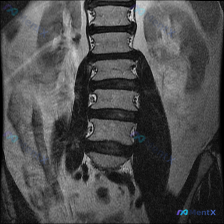

整理到一份腰椎MRI-T1序列-冠状位的影像资料,有人第一眼先提到了“脊柱侧弯”的可能性。 先放影像里的关键描述: - 腰椎椎体序列尚可,未见明显的椎体楔形变或压缩性骨折 - 脊柱冠状位对线基本居中,未见显著的脊柱侧弯畸形 - 椎间隙高度基本维持,终板轮廓尚清晰 - 双侧腰大肌及竖脊肌群信号均匀,未...